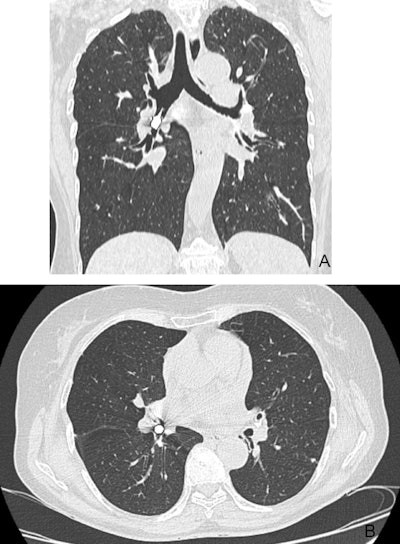

Then a CT scan was completed to get a precise location of the drill head. The scan confirmed that the drill head was in the intermediate bronchus and extended into the inferior bronchus on the right side.

Figure 2: Thoracic CT scan showing the drill head located in the right intermediate and right lower bronchi. (A) coronal view (B) axial view.